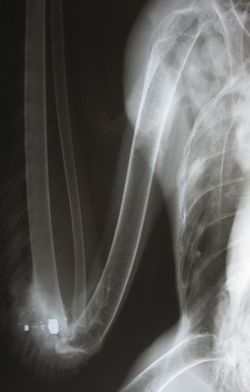

An x-ray told veterinarian Victoria Vosberg all she needed to know about this injured bald eagle, which was found by residents of a trailer park near the Indian River on May 16. The large white object is a bullet or pellet; the small white objects are fragments. The fuzziness around the image suggests an extensive infection. This female had a brood patch; she was likely nesting when she was shot. Raptor center staff were unable to save her.